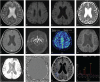

Rationale: Neuronal intranuclear inclusion disease (NIID) is a rare neurodegenerative disease identified with diffusion-weighted imaging (DWI) high-intensity signal in magnetic resonance imaging (MRI). The disappearance of the abnormal signal is extremely rare.

Diagnoses: DWI high-intensity signal were observed along the corticomedullary junction in MRI plan scan of heads of 2 patients. For patient 1, the hyperintensities in DWI and fluid-attenuated inversion recovery (FLAIR) images in the occipital lobe disappeared 5 years after onset. Based on the biopsy, patient 1 and 2 were diagnosed as NIID.

Lessons: DWI high-intensity signal is a strong clue for the diagnosis of NIID, but the rare case of the disappearance of it may lead to misdiagnosis.